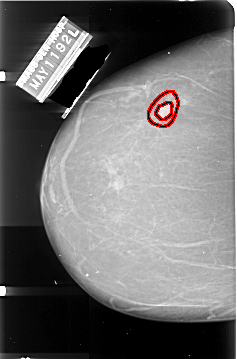

A_1004_1.LEFT_MLO

FILE: A_1004_1.LEFT_MLO.OVERLAY

TOTAL_ABNORMALITIES 1

ABNORMALITY 1

LESION_TYPE MASS SHAPE IRREGULAR MARGINS SPICULATED

ASSESSMENT 5

SUBTLETY 5

PATHOLOGY MALIGNANT

TOTAL_OUTLINES 2

BOUNDARY

CORE